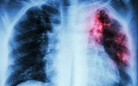

Всемирный день борьбы с туберкулезом отмечается ежегодно 24 марта – в день, когда в 1882 году микробиолог Роберт Кох объявил о сделанном им открытии возбудителя туберкулезной инфекции. Туберкулез все еще остается самым смертоносным инфекционным убийцей в мире, делятся в Департаменте: от этой болезни во всем мире умирает больше больных, чем от всех инфекционных и паразитарных болезней вместе взятых.